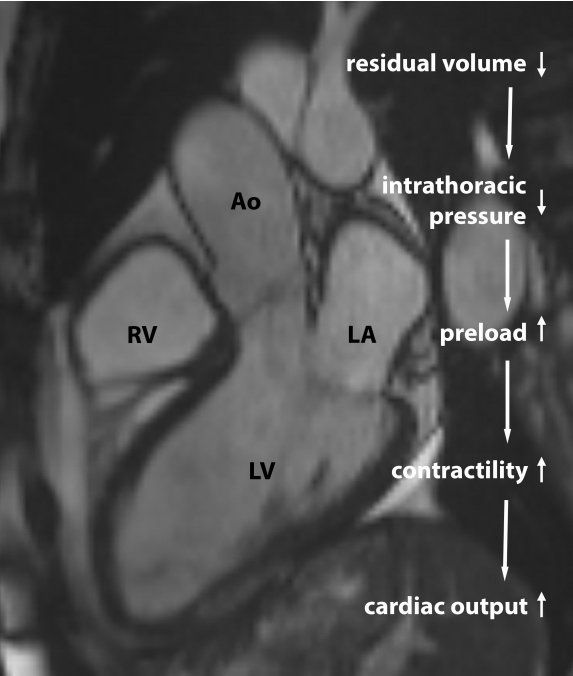

Reduction of lung hyperinflation using lung volume reducing endobronchial valves improves cardiac preload, myocardial contractility and cardiac output in patients with

#COPD and severe emphysema@LVanfleteren@ATSBlueEditor https://doi.org/10.1164/rccm.202201-0214OC …pic.twitter.com/DDJJQxEBfk